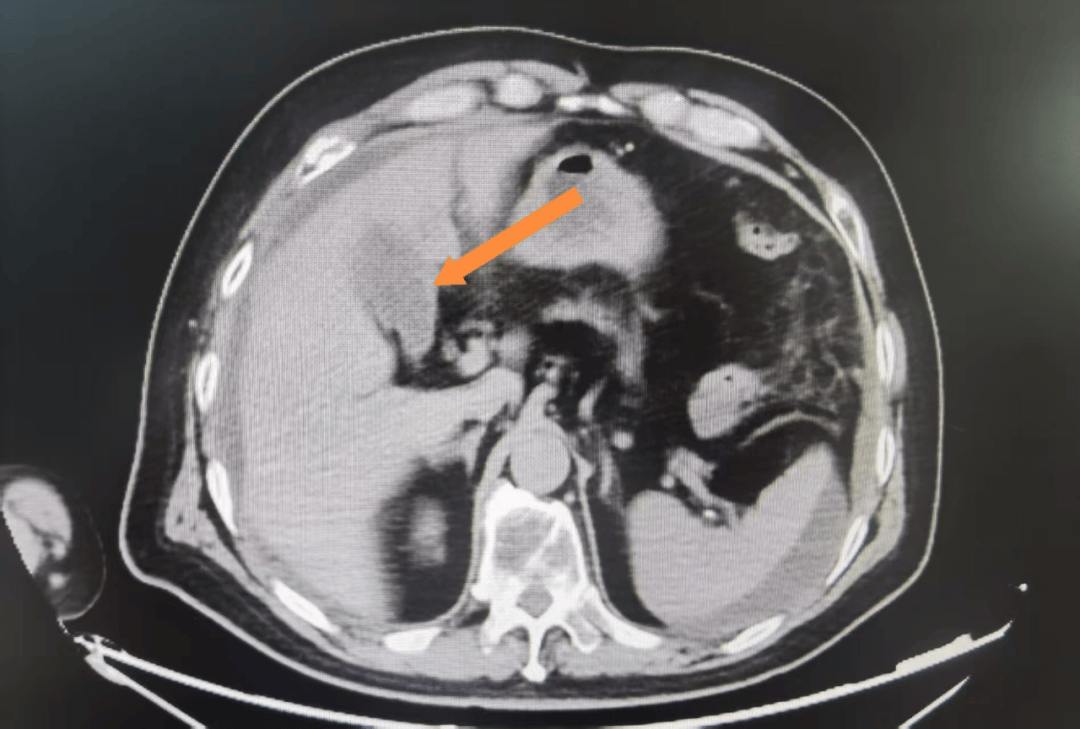

【病例】胆囊腺肌症1例ct影像表现

【病例】胆囊腺肌症1例ct影像表现 – 影像ppt